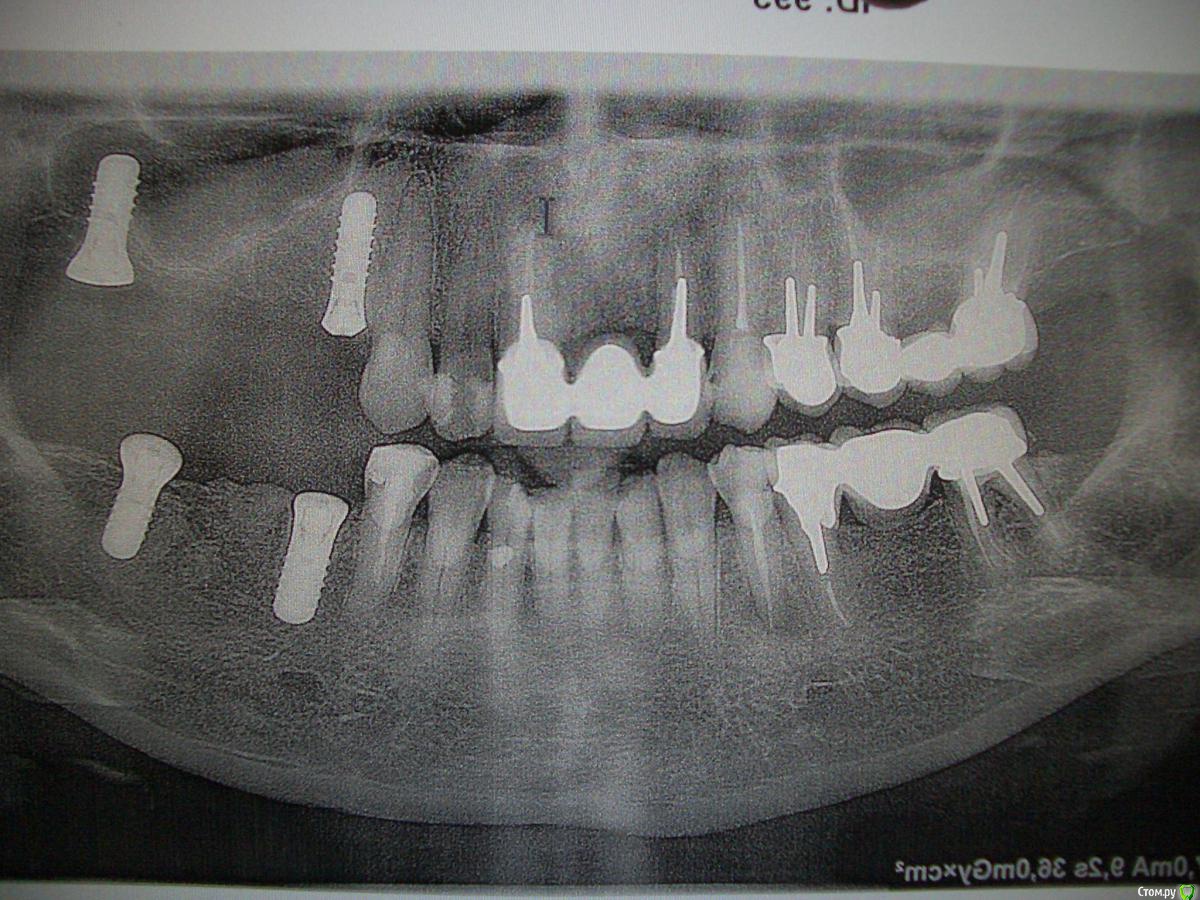

lankal Опубликовано 22 декабря, 2016 Поделиться Опубликовано 22 декабря, 2016 Здравствуйте, уважаемые врачи!Два месяца назад были установлены 4 имплантанта Штрауман. Снимок сделан 1 месяц и 3 недели после имплантации. На верхней 4-ке был синуслифтинг точно (я терпела как-будто что-то забивали, в описании операции, прилагаемом ниже, врач почему-то пишет , что на 7-ке вверху). Хочу проконсультироваться с Вами: правильно ли поставлены имплантанты? Не очень ли близко верхняя 4-ка к корням зуба (зуб пока не беспокоит)? И что на данный момент у меня с верхней 7-кой, она в гаймаровой пазухе? Мой врач ничего не говорит, "клещами вытащила" из него фразу "есть небольшие опасения", но при этом на протезирование планирует дать "добро" в феврале. Очень жду Вашего мнения! Ссылка на комментарий

Jurai Опубликовано 22 декабря, 2016 Поделиться Опубликовано 22 декабря, 2016 относительно зуба 13 имплантат в позиции 14 расположен хорошо, до корня и до синуса расстояние приличное, синуслифтинга там явно не было и не нужен был. Синуслифтинг был в области седьмого,по этому снимку точно не сказать удачен или нет. Хотите ясности - сделайте КТ. 1 Ссылка на комментарий

lankal Опубликовано 22 декабря, 2016 Автор Поделиться Опубликовано 22 декабря, 2016 Спасибо за ответ! Упс, я снимок задом наперёд сфотографировала , имплантация у меня слева была Подскажите, если сейчас КТ сделать, информативно будет или подождать еще какое-то время целесообразно? Остеопластические материалы написано в выписке не применялись. Закрытый синуслифтинг был с целью приподнять пазуху - это слова доктора. Что мне грозит в случае неудачи в области седьмого? Воспаление и переимплантит? Ссылка на комментарий

колесников Опубликовано 22 декабря, 2016 Поделиться Опубликовано 22 декабря, 2016 Что мне грозит в случае неудачи в области седьмого? Воспаление и переимплантит? может не выдержать нагрузки. Закрытый синуслифтинг также подразумевает увеличение объема кости. Рекомендовал бы добавить еще имплант в области 15. Ссылка на комментарий

lankal Опубликовано 22 декабря, 2016 Автор Поделиться Опубликовано 22 декабря, 2016 Добавить можно, но где гарантия, что в области седьмого будет все нормальтно. Может его удалить, ведь он наполовину в пазухе и могут начаться осложнения? Ссылка на комментарий

Bier Опубликовано 22 декабря, 2016 Поделиться Опубликовано 22 декабря, 2016 Не факт, что в пазухе. Надо кт сделать, будет видно где он. Ссылка на комментарий